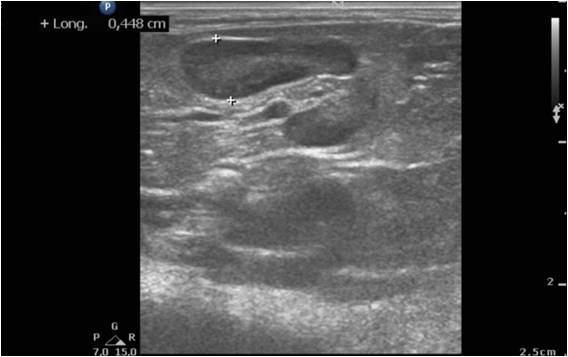

Lorsque les glandes surrénales sont fortement stimulées, elles deviennent progressivement hyperplasiques puis tumorales (tumeur bénigne puis maligne). Le diagnostic peut être établi par échographie, réalisée par un vétérinaire expérimenté avec les furets, et par une prise de sang (dosage des hormones en question). Suivant l'extension et la présence ou non d'embole vasculaire, il est recommandé de poser un implant hormonal ou de réaliser une surrénalectomie. Cette chirurgie est particulièrement risquée à cause de la proximité des glandes surrénales avec l'aorte, un vaisseau sanguin vital pour l'organisme. Il peut être utile d'utiliser des outils de microchirurgie ainsi que du matériel de pointe tel qu'une caméra endoscopique per-opératoire Vitum pour maximiser la réussite de la chirurgie.

Le diagnostic se fait par prise de sang et par échographie, réalisée par un vétérinaire expérimenté. Parfois, un traitement doit être administré en urgence, car les crises d'hypoglycémie peuvent être mortelles. Une hospitalisation est nécessaire en cas de crises convulsives. Les premières phases du traitement sont médicales mais une chirurgie (pancréatectomie) peut être recommandée dans certaines formes d'insulinome. Nous utilisons pour ce faire la technologie Ligasure pour minimiser le temps opératoire et les risques associés à l'opération.